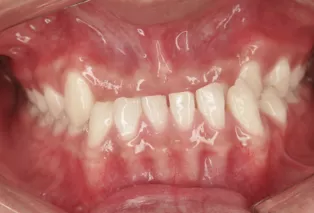

Photos intra-orales